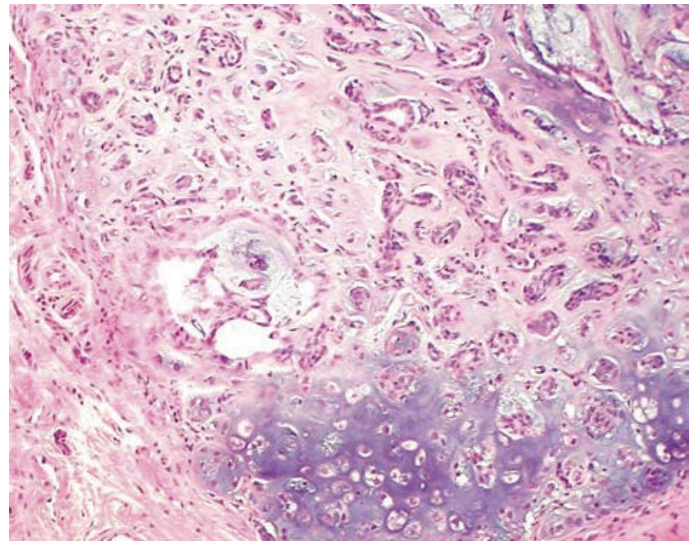

왼쪽은 fibroma, 오른쪽은 fibrosarcoma

- ex) fibroma: fibroblast orgin의 양성 종양 / fibrosarcoma: fibroblast의 악성 종양